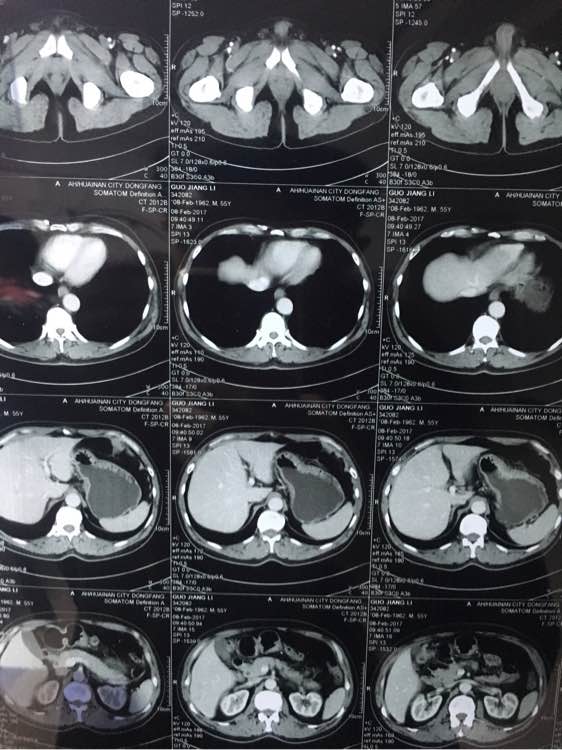

大神看下,几个月前说肠子

ct吧

几个月前说有点东西,肠子上

兄弟 你拍的有点多啊 全腹部ct?